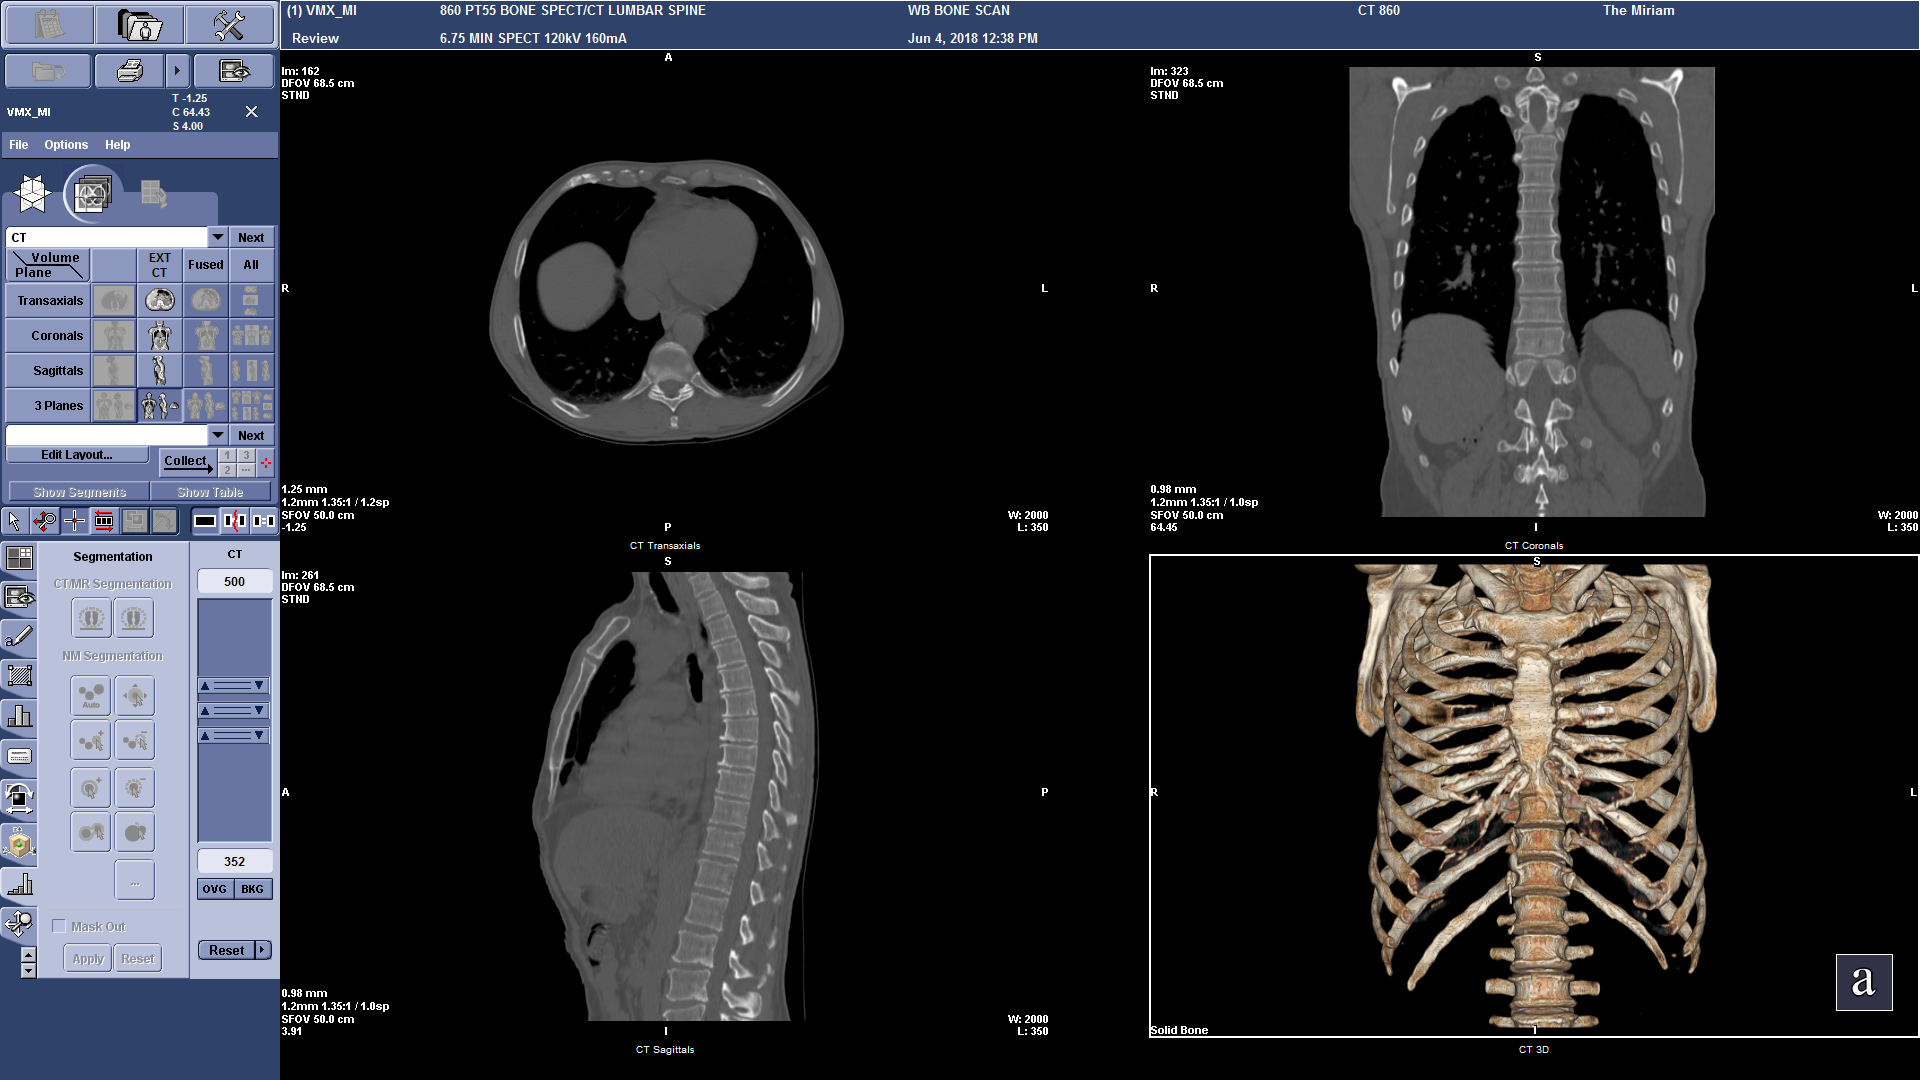

All our new 800 Series SPECT/CT systems build on the success of the 600 Series with a collection of SPECT technology enhancements that add to the value of nuclear medicine. In addition to the all-new SmartConsole, these enhancements include a new LEHRS (Low Energy High Resolution and Sensitivity) collimator, which can be combined with either SPECT Step & Shoot Continuous scanning mode or our Planar Clarity 2D processing to increase sensitivity and enable a reduction of scan times or injected dose1. It’s called SwiftScan Planar and SwiftScan SPECT. NM/CT 860 also includes the Elite NXT detectors, designed to address some of nuclear medicine’s biggest challenges.

We paired these great SPECT enhancements with our Revolution™ ACTs CT system. It’s an eight-slice CT system with fine resolution and contrast, as well as IQ Enhance, a reconstruction technology that makes it possible to scan at a faster helical pitch to cover more anatomy at similar image quality. This combination of imaging technologies allows you to provide both advanced SPECT/CT exams and the most common overflow standalone CT exams.